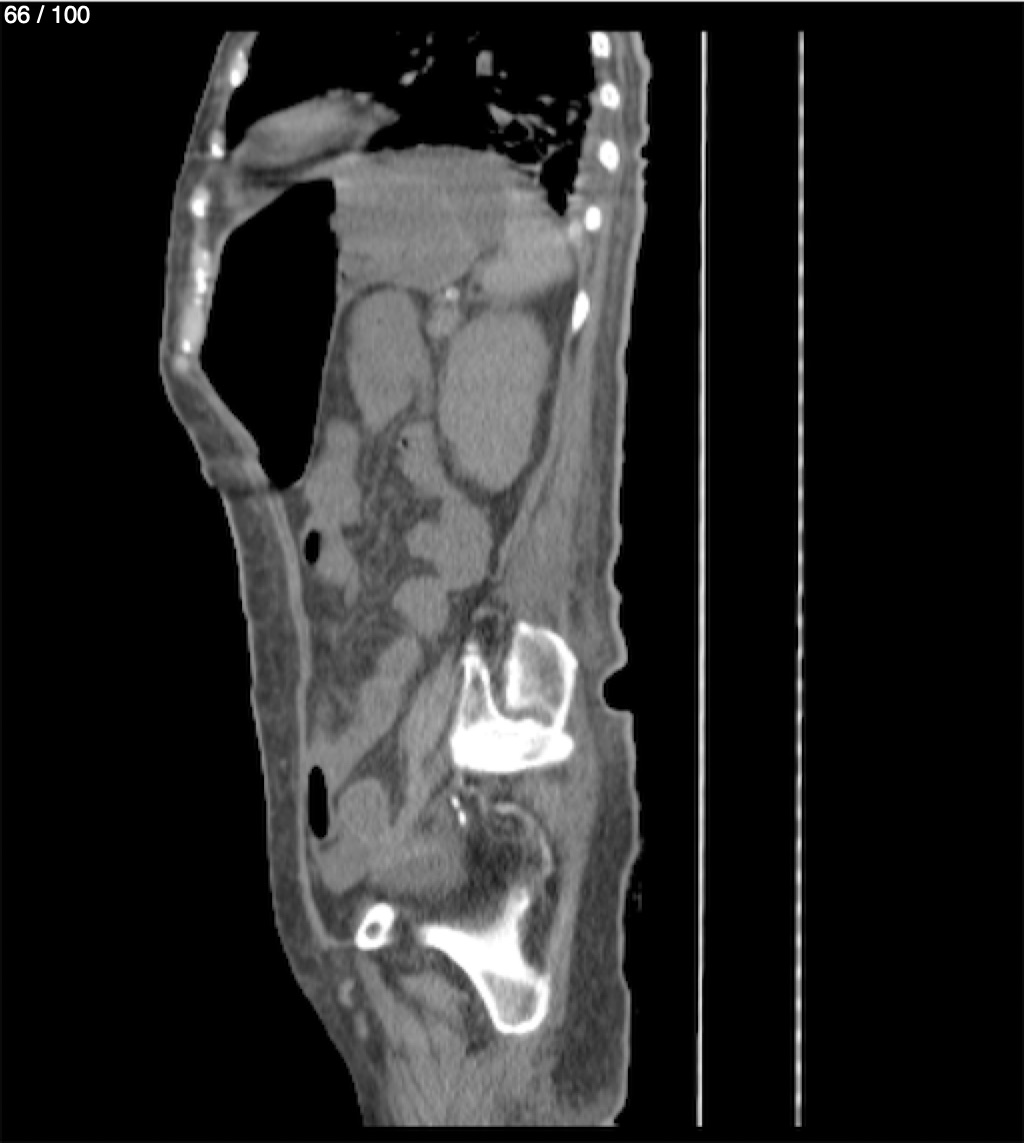

Hilda Geronimo Mendez 60A - T.C Abdomen Simple